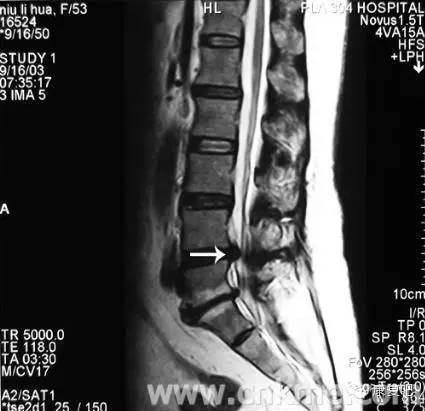

3、核磁共振攝影(MRI)

可顯示出狹窄的部位(脊髓腔的狹窄)、椎間盤物質的突出進入脊髓腔、或受侵害之脊髓神經(jīng)根。